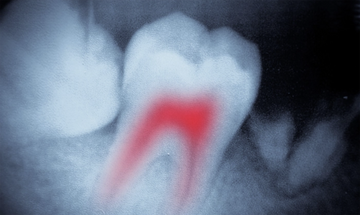

By focusing on these critical areas, Unitein Gum Restore Toothpaste helps safeguard the health of not only the gums but also the entire oral cavity, providing a proactive solution for those with root canal-treated teeth to maintain their oral and overall health.